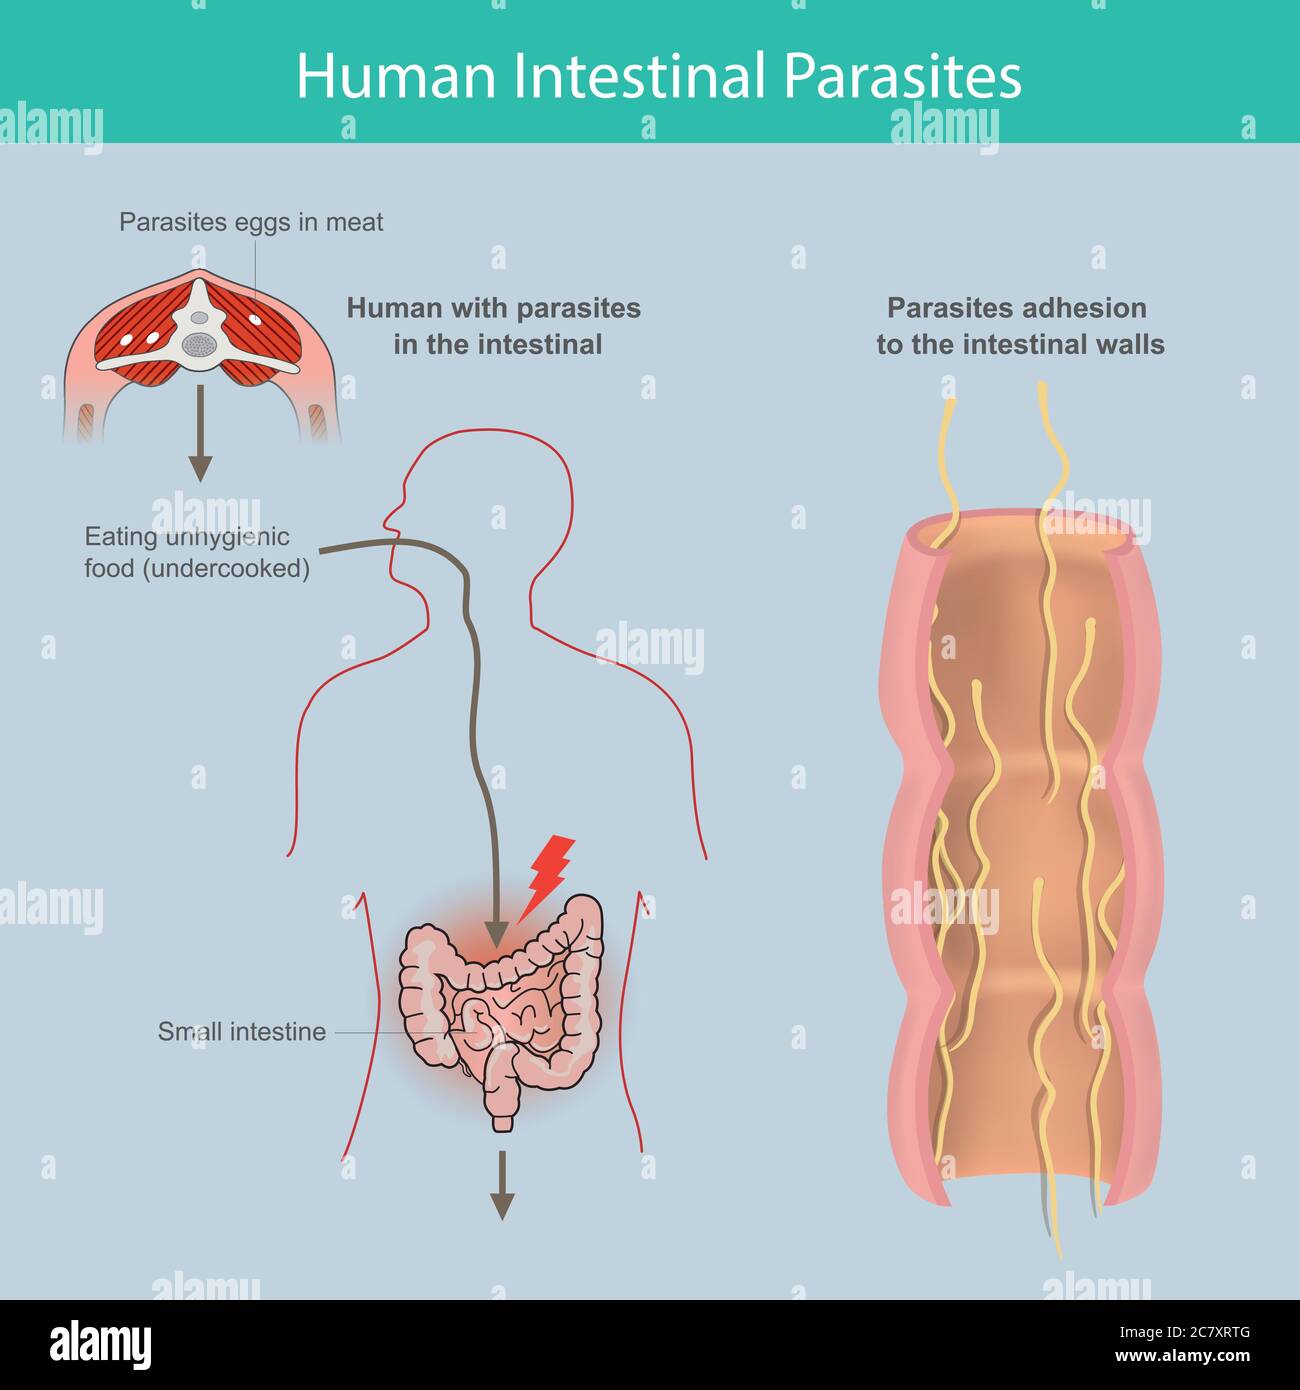

Parasiti intestinali umani. Illustrazione spiegare i parassiti nell'intestino tenue umano per causa di mangiare carne infetta o uova parassitarie nella carne Illustrazione Vettorialehttps://www.alamy.it/image-license-details/?v=1https://www.alamy.it/parasiti-intestinali-umani-illustrazione-spiegare-i-parassiti-nell-intestino-tenue-umano-per-causa-di-mangiare-carne-infetta-o-uova-parassitarie-nella-carne-image366309792.html

Parasiti intestinali umani. Illustrazione spiegare i parassiti nell'intestino tenue umano per causa di mangiare carne infetta o uova parassitarie nella carne Illustrazione Vettorialehttps://www.alamy.it/image-license-details/?v=1https://www.alamy.it/parasiti-intestinali-umani-illustrazione-spiegare-i-parassiti-nell-intestino-tenue-umano-per-causa-di-mangiare-carne-infetta-o-uova-parassitarie-nella-carne-image366309792.htmlRF2C7XRTG–Parasiti intestinali umani. Illustrazione spiegare i parassiti nell'intestino tenue umano per causa di mangiare carne infetta o uova parassitarie nella carne